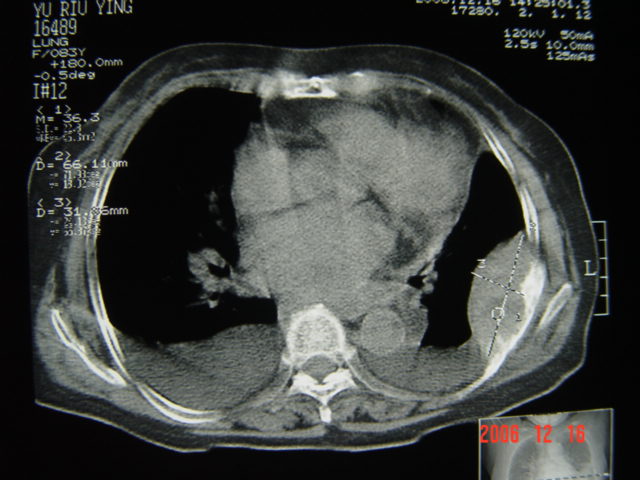

标题: CT5663:女、83岁,轻微咳嗽、左下胸痛。 [打印本页]

标题: CT5663:女、83岁,轻微咳嗽、左下胸痛。

左第八肋腋侧呈膨胀性骨质破坏,内侧见软组织密度肿块。左肺舌段呈楔形实变,基底近胸壁,尖端向肺门。双侧胸壁后缘见新月形水样密度区。

考虑:1、左第8肋骨转移瘤;

2、左肺舌叶肺栓塞可能性大;

3、双侧中量胸腔积液。

考虑:1、左第8肋骨转移瘤;恶性间皮瘤?